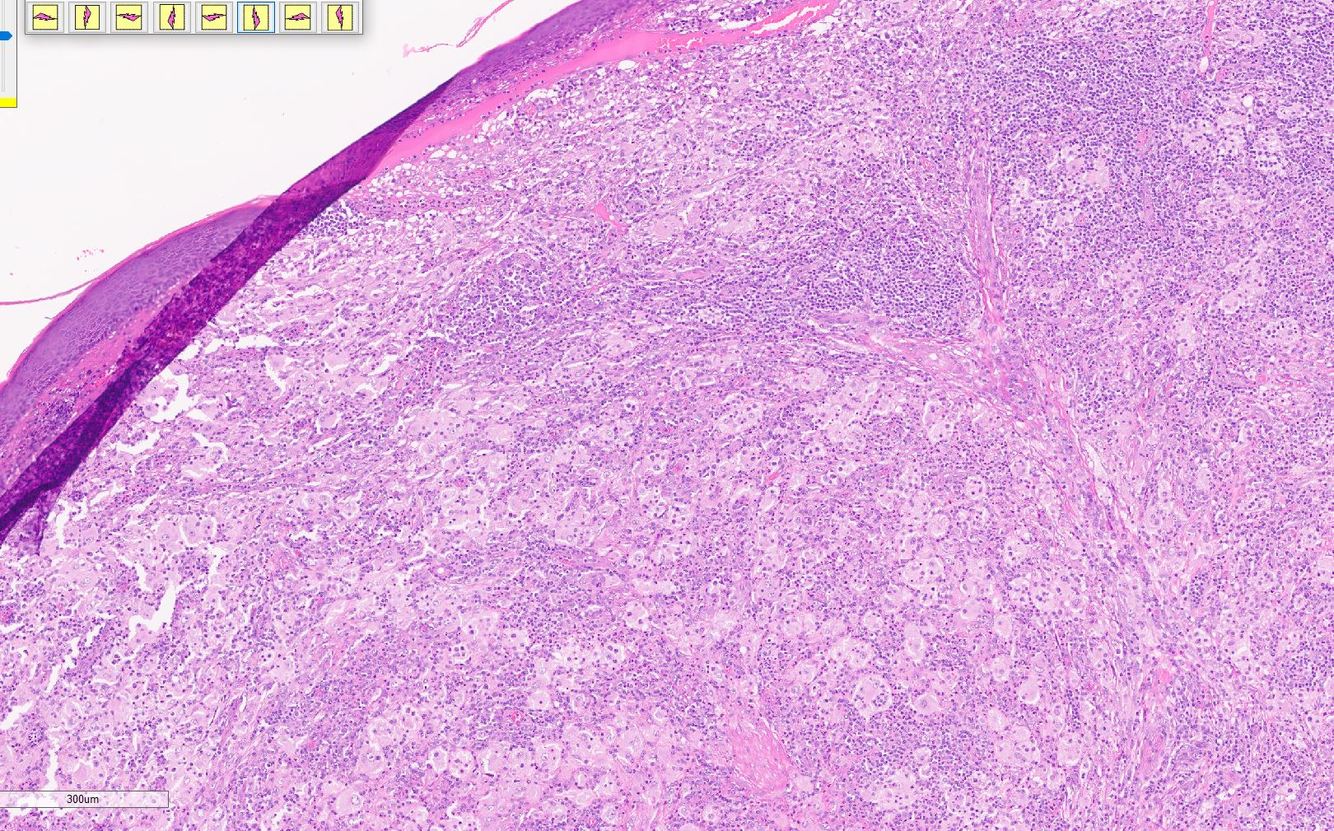

Rosai Dorfman

Fibrotic nodules showing light and dark areas

Sheets of histiocytes (light areas) with nodules of lymphoytes (dark areas)

Emperipolesis (intact cells, especially lymphocytes and plasma cells, passing through histiocytes)

S100 positive, CD1a negative, CD68 positive